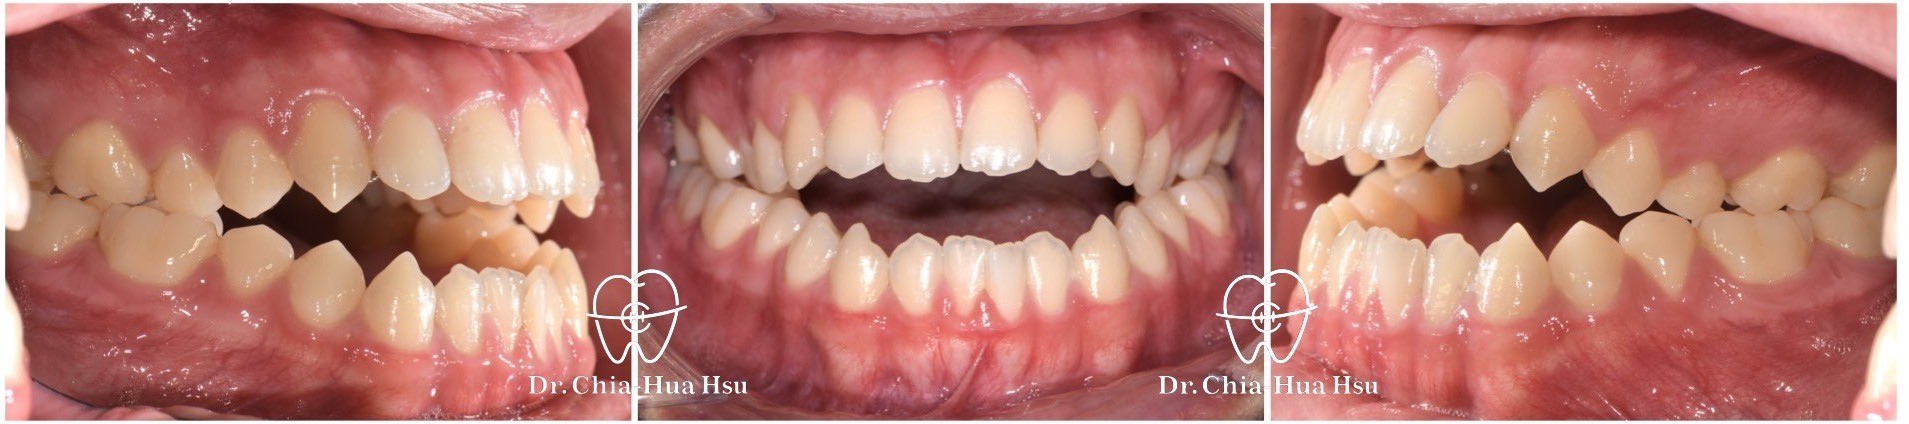

戽斗、開咬、齒列不正

• 病患主訴:戽斗、前牙開咬。

• 問題分析:患者是標準的骨骼三類咬合(Skeletal Class III),下巴明顯較長,還有上顎牙弓過窄、開咬以及齒列不正。

• 治療方式:使用傳統金屬矯正器,合併正顎手術(雙顎),上顎拔除兩顆小臼齒以利手術方式進行上顎牙弓擴寬。

• 治療時間:1 年 7 個月。

• 治療結果:齒列排齊,咬合功能恢復,外觀更和諧。

治療前

治療後